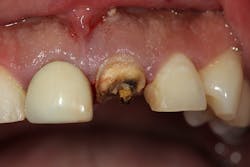

• Type 2 socket (figures 10a and 10b)—Buccal plate missing, but soft tissue present: bone graft +/- membrane (if graft containment is needed)